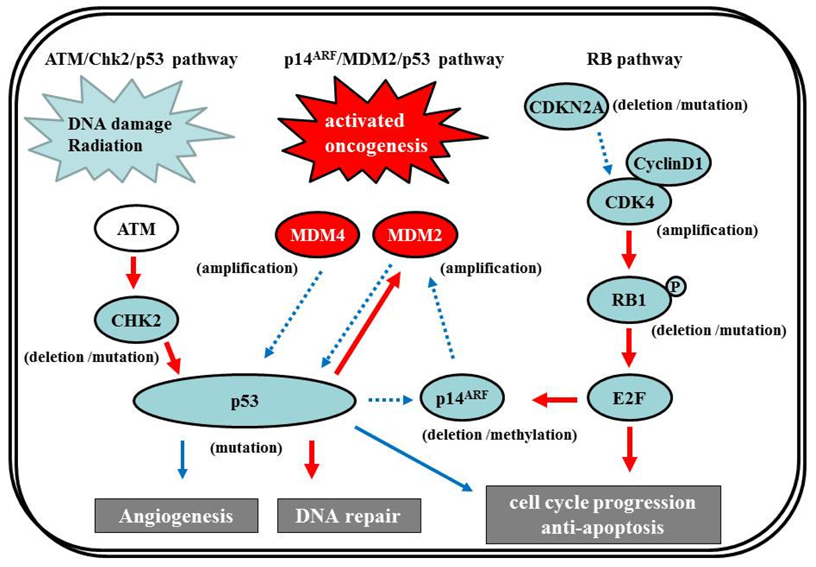

The p53 gene, at chromosome 17q13.1, encodes a protein that responds to diverse cellular stresses to regulate target genes that induce cell cycle arrest, cell death, cell differentiation, senescence, DNA repair, and neovascularization [111]. Following DNA damage, p53 is activated and induces transcription of genes such as p21Waf1/Cip1 that function as regulators of cell cycle progression at G1 phase [10,112,113]. The MDM2 gene, at chromosome 12q14.3-q15, encodes a putative transcription factor and enhances the tumorigenic potential of cells when it is overexpressed. Forming a tight complex with the p53 gene, the MDM2 oncogene inhibits p53 transcriptional activity by binding to the N-terminal transactivation domain, and participates in the ubiquitination and proteasomal degradation of p53 [114,115]. Conversely, the transcription of the MDM2 gene is induced by wild-type p53 [116,117]. This autoregulatory feedback loop regulates the expression of MDM2 and the activity of p53. The p14ARF (a part of the complex CDKN2A locus on chromosome 9p21) gene encodes a protein that directly binds to MDM2 and inhibits MDM2-mediated p53 degradation and transactivational silencing [113,118-120]. In turn, p14ARF expression is negatively regulated by p53 [113]. Thus, inactivation of p14ARF/MDM2/p53 is caused by altered expression of any of the p53, MDM2, or p14ARF genes (Figure 7).

The p53 pathway plays a crucial role in the development of secondary GBMs. IDH1 gene mutations at chromosome 2q33, which were identified in an analysis of 20,661 protein-coding genes in GBMs [1], are early events in the development of astrocytomas and constitute a remarkably reliable molecular signature of secondary GBMs as well as their precursor lesions [122-124]. The additional acquisition of a p53 mutation, which is a genetic event subsequent to the IDH1/2 mutations except in the case of Li-Fraumeni syndrome [125], may lead to astrocytic differentiation, while subsequent loss of 1p/19q favors the acquisition of an oligodendroglial phenotype [123,126]. GBMs with IDH1/2 mutations frequently have p53 mutations, which are significantly associated [122]. p53 mutations are also common in two-thirds of precursor low-grade diffuse astrocytomas; this frequency is similar to that in anaplastic astrocytomas and secondary GBMs [28,84,127]. p53 mutations also occur in primary GBMs, but at a significantly lower frequency (approx. 25%) [128]. In secondary GBMs, 57% of p53 mutations are located in the hotspot codons 248 and 273; however, in primary GBMs, mutations are more equally distributed through all exons, with only 17% occurring in codons 248 and 273. The less-specific pattern of p53 mutations may constitute, at least in part, secondary events owing to increasing genomic instability during tumor development.

The p53 gene is the most commonly mutated p53 pathway gene in glioma; however, molecular abnormalities involving other genes in the pathway—Such as p14ARF, MDM2, or MDM4—have also been described. MDM2 amplification is observed in about 10% of GBMs, exclusively in primary GBMs that lack a p53 mutation [12,129]. Loss of p14ARF expression is frequently present in GBMs. p14ARF appears to be associated mostly with aberrant promoter methylation or hemizygous deletion, whereas mutational inactivation is rare [130,131]. Promoter methylation of p14ARF is more frequent in secondary than primary GBMs, but there is no significant difference in the overall frequency of p14ARF alterations between GBM subtypes [131].

7.2.2 ATM/Chk2/p53 pathway

Recently, in addition to the p14ARF/MDM2/p53 pathway, the ATM/Chk2/p53 pathway has come under the spotlight. Squatrito et al. reported that loss of the ATM/Chk2/p53 pathway components accelerates glioma development and contributes to radiation resistance [132]. In response to ionizing radiation, cells activate the sensor kinases ATM, ATR, and DNA-PK, a DNA-dependent protein kinase [133,134] that phosphorylates multiple downstream mediators, including the checkpoint kinases Chk1 and Chk2 [135,136], resulting in cell-cycle checkpoint initiation and/or apoptosis. Chk2, at chromosome 22q12.1, can regulate p53-dependent apoptosis in an ATM-independent manner as a tumor suppressor [137,138] (Figure 7). Although previous studies reported no or low frequency of Chk2 mutations (approx. 6%) [139,140], 22% of glioma patients in the TCGA study presented single-copy loss of the chromosomal region containing Chk2, with a significant reduction of Chk2 mRNA, suggesting that it might represent an important tumor suppressor in a subset of glioma patients [1,132].

7.3. RB Pathway

The RB pathway suppresses cell cycle entry and progression, as well as the p53 pathway. The 107-kDa RB1 protein encoded by RB1 (at 13q14) controls progression through G1 into the S-phase of the cell cycle [9]. The CDKN2A (p16INK4a) protein binds to CDK4 and inhibits the CDK4/cyclin D1 complex, thus inhibiting cell cycle transition from G1 to S phase (Figure 7) [10,12]. Thus, alteration of RB1, CDK4, or CDKN2A can cause dysregulation of the G1-S phase transition. Inactivation of this pathway is commonly observed in both primary and secondary GBMs [12]. Genetic loss of RB1 (40%), homozygous deletion of CDKN2A (40%), and/or CDK4 amplification (15%) are detected in the majority of GBM (80%) [11,141], and appear to be roughly mutually exclusive [11,12,142-144]. The TCGA pilot project revealed that the frequency of genetic alterations in the RB signaling pathway was 77%, containing CDKN2A homozygous deletion or mutations (52%), CDKN2B (p15INK4b) homozygous deletion (47%), CDKN2C (p18INK4c) homozygous deletion (2%), CDK4 amplification (18%), CCND2 (cyclin D2) amplification (2%), CDK6 amplification (1%), and RB1 mutation or homozygous deletion (11%) [1]. Alteration of only the Rb pathway is insufficient to induce tumor formation. EGFR amplification enhances the PI3K pro-growth pathway and is typically associated with CDKN2A deletions [145,146]. CDKN2A loss is associated with the classical subtype of GBM, according to the TCGA study [1].